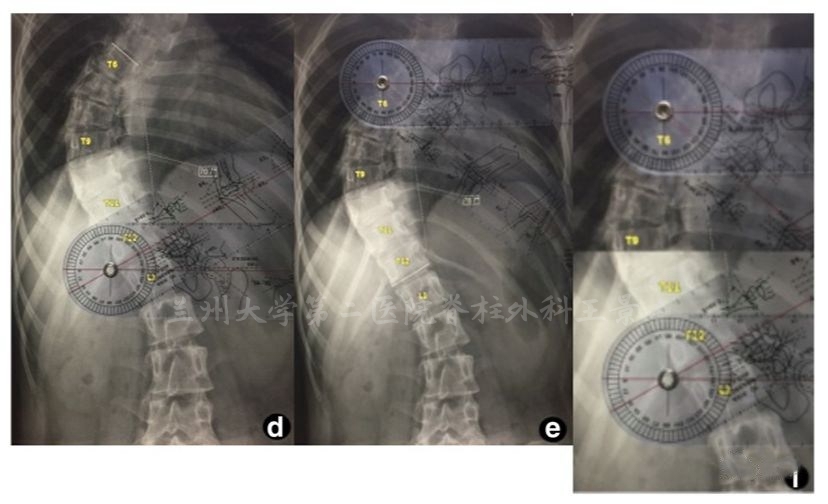

经典Cobb角测量是

分别做上、下端椎终板连线(UEVEL/LEVEL)的垂线

两条垂线的相交角度即是Cobb角

现在通过简单的几何证明

上、下端椎倾斜角度之和(α+β)

就是脊柱侧弯Cobb角

测量上下端椎倾角(End Vertibra Tilt Angle,EVTA)

就可以简便快速得出

脊柱侧弯Cobb角结果

比经典测量法至少快30%

画线少,胶片污损更小

量角器底边放胶片上摆平

角度刻度线与端椎终板吻合后直接读数

水平线都不用画了,几秒钟时间